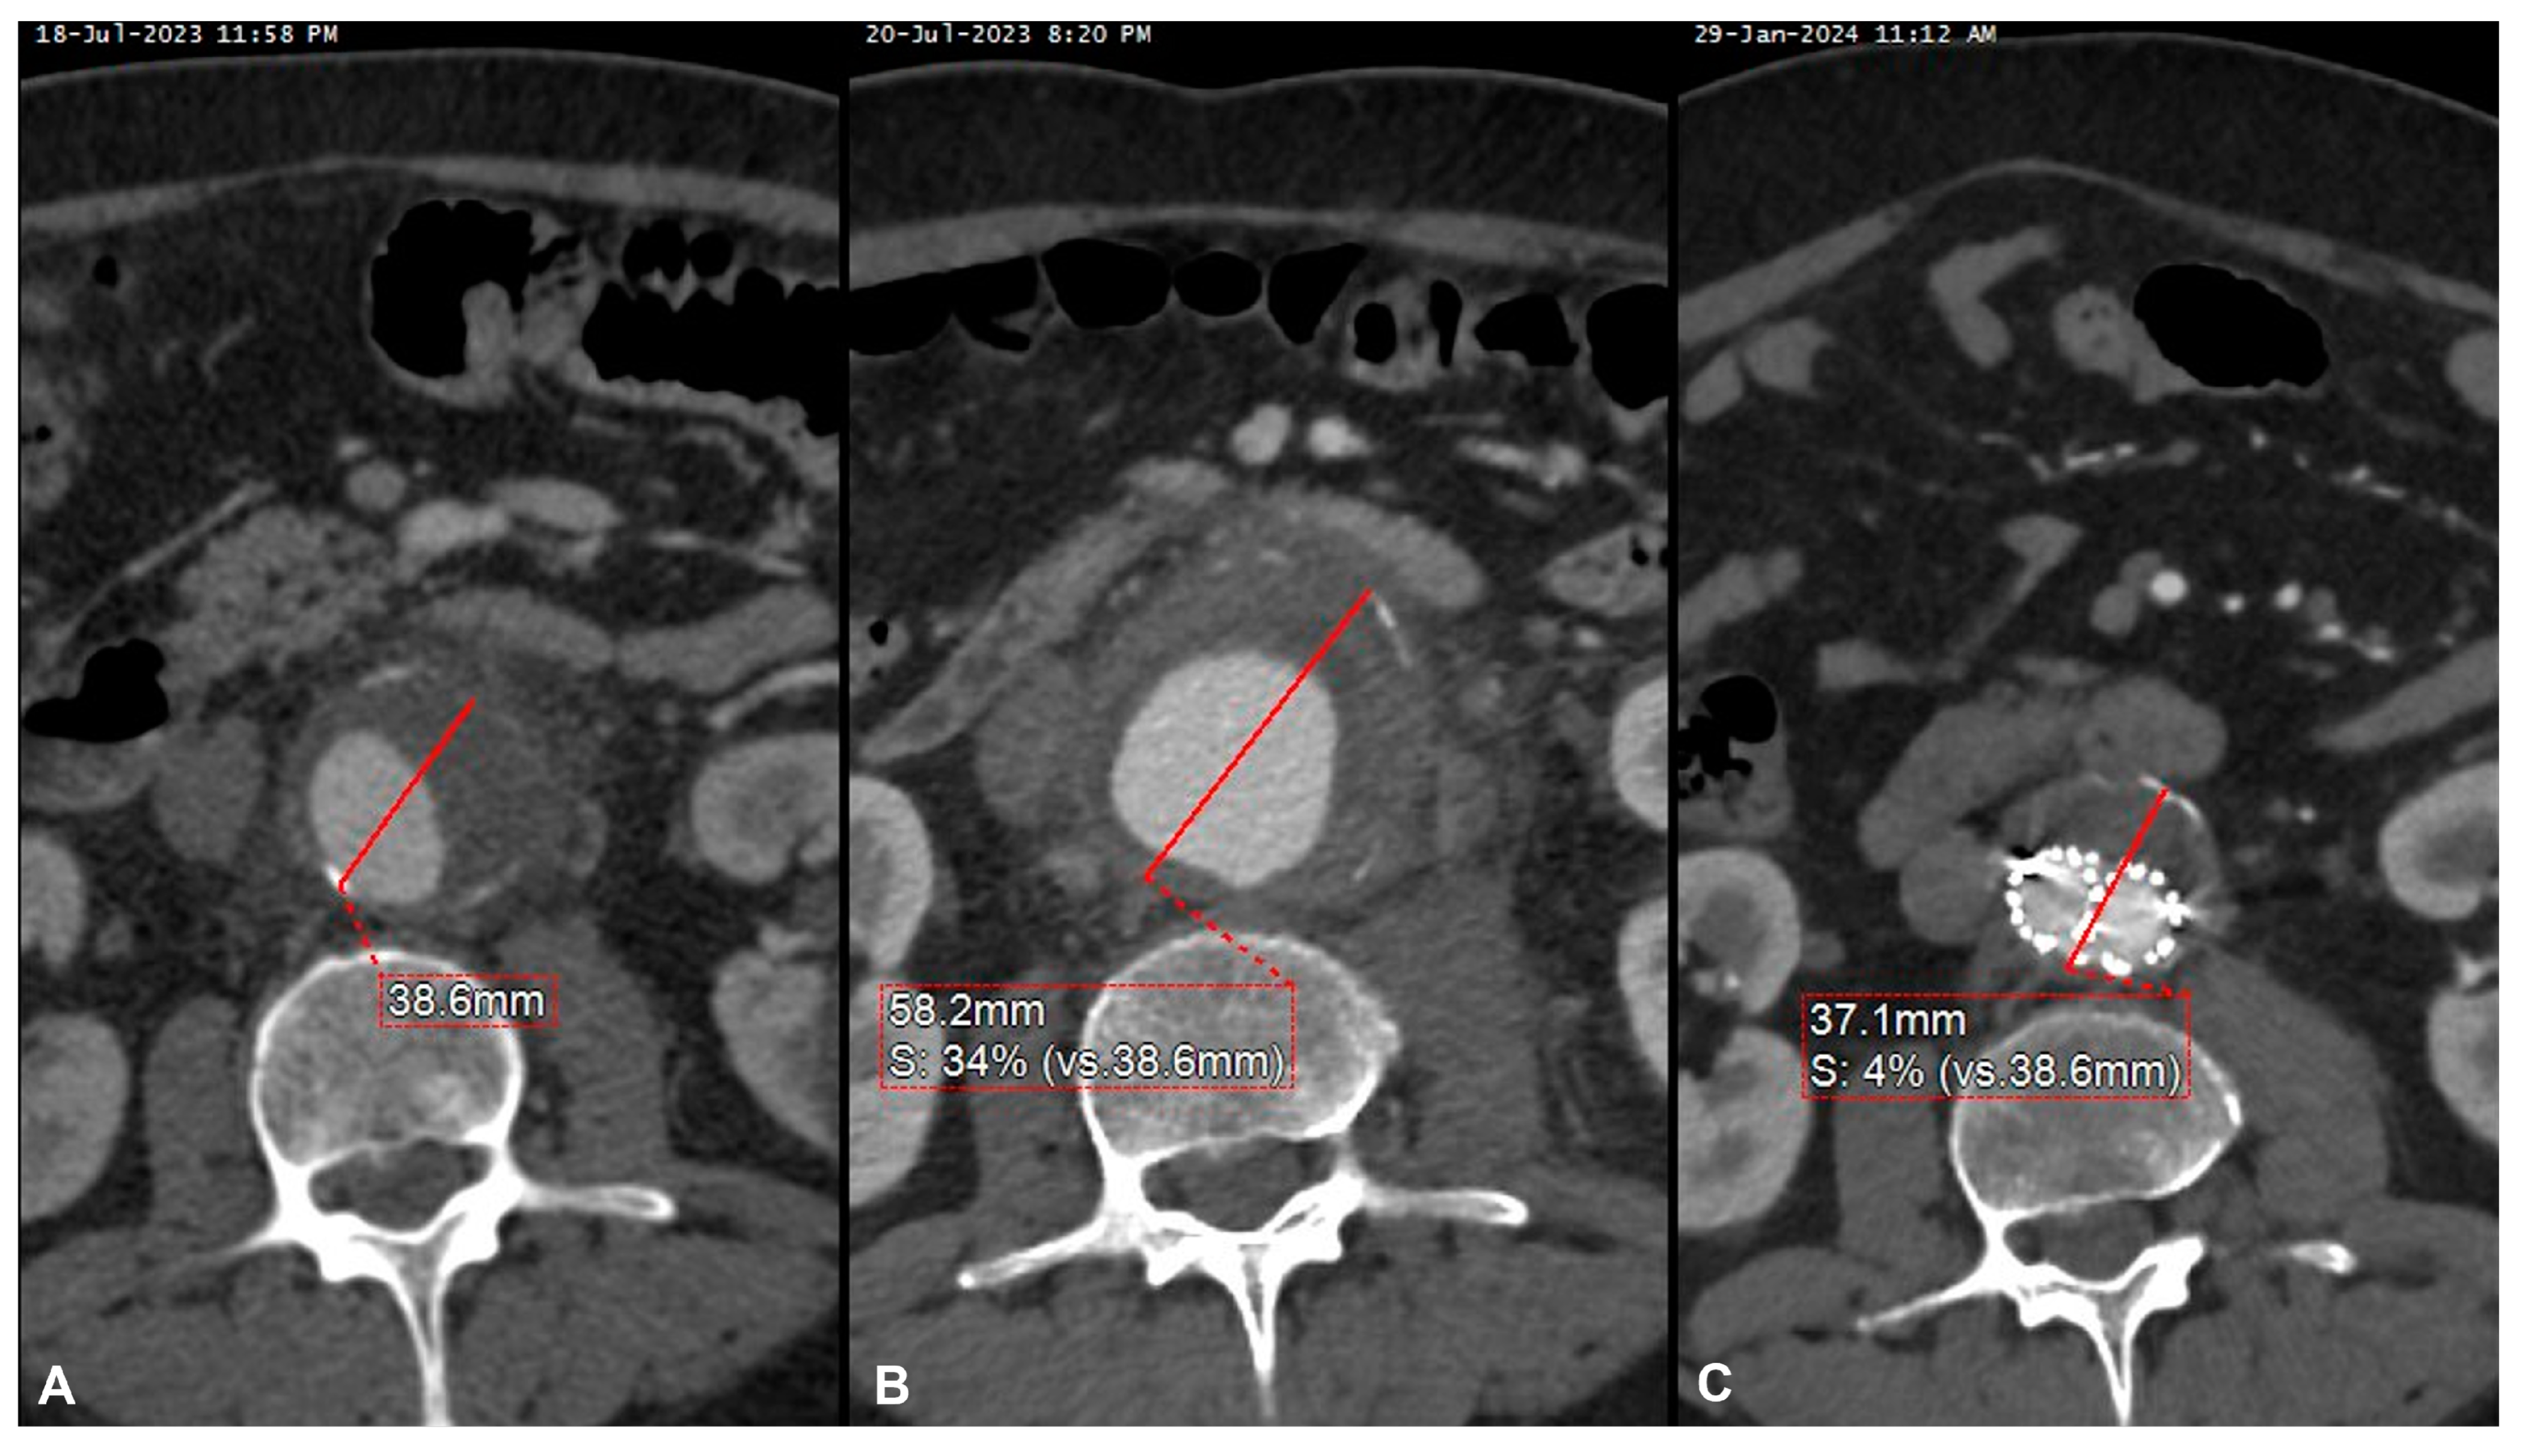

Although the clinical presentation may widely vary, the most common presentation in our sample was a rapidly growing aneurysm, with symptoms of abdominal or back pain, with evidence of contained or free rupture in half of the cases. This required a prompt interventional management in all of our patients, in addition to antibiotic therapy (Figure 3).

Figure 3. Pre-operative computed tomography angiography (CTA) of symptomatic small abdominal aortic aneurysm (A) and 2-day CTA performed for persistent pain showing a 20 mm aneurysm’s growth (B), urgently treated with EVAR with a good clinical and radiological result, as demonstrated by the significant aneurysm’s shrinkage noted at the 6-month postoperative CTA (C).